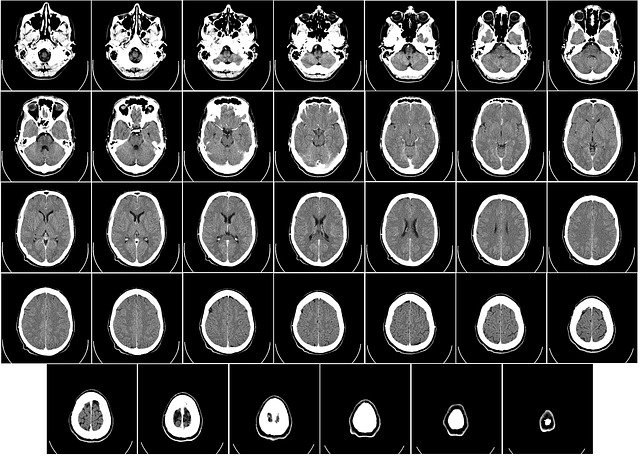

조영제를 투여하게 되면 병변의 윤곽형태를 보다 선명하게 관찰할 수 있어, 촬영으로 인한 진단을 보다 정확하게 할 수 있는 장점이 있는데요. 사용부위로는 뇌, 폐, 위, 간 등... 거의 모든 내장기관의 질환과 손상을 파악하는데 이용됩니다.